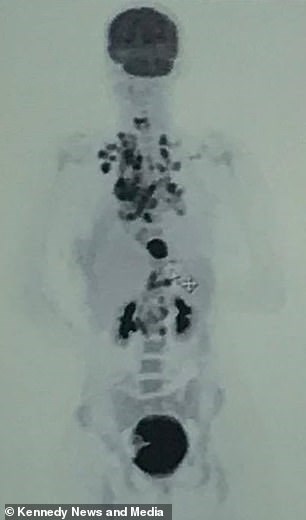

Οι γιατροί έδωσαν στη Σάντερσον μόλις ημέρες ζωής ενώ οι αγαπημένοι της άρχισαν να συγκεντρώνουν χρήματα μέσω πλατφόρμας για της κάνουν την κηδεία που θα ήθελε. Και ξαφνικά, οι γιατροί έμειναν άναυδοι όταν αντίκρισαν τα αποτελέσματα της εξέτασής της καθώς δεν υπήρχε δείγμα από όγκο και λίγο αργότερα η κοπέλα κρίθηκε θεραπευμένη.

Η κοπέλα είχε όγκους σε όλο τον θώρακα και έτσι ξεκίνησε αμέσως χημειοθεραπείες. Έπειτα από δύο γύρους φάνηκε ότι οι μικρότεροι όγκοι είχαν εξαφανιστεί, ωστόσο υπήρχε μία τεράστια μάζα που ανησυχούσε τους γιατρούς καθώς θεωρούσαν ότι η θεραπεία δεν είναι αρκετή. Έτσι η ασθενής υποβλήθηκε σε ακόμη πιο δυνατό κύκλο χημειοθεραπειών και στη συνέχεια, εξαντλημένη, αποφάσισε ότι δεν μπορεί να περάσει άλλο αυτό.

Στον ναό θα μετέφερε το φέρετρό της άλογο με άμαξα. Έφτιαξε ακόμη και λίστα μουσικής που θα έπαιζε στο ύστατο χαίρε. Αρχές Ιανουαρίου ένας φίλος δημιούργησε το ταμείο αλληλεγγύης για τα έξοδα κηδείας. Ήταν τέλος του μήνα που η 19χρονη άρχισε να αισθάνεται καλύτερα και επέστρεψε στο νοσοκομείο ζητώντας νέα μαγνητική. Πράγματι έκανε τη μαγνητική στις 18 Μαρτίου και στις 25 πήρε τα αποτελέσματα. Οι γιατροί της ανακοίνωσαν ότι ο οργανισμός της ήταν πενταξάθαρος και δεν υπήρχε ίχνος όγκου στον θώρακα.